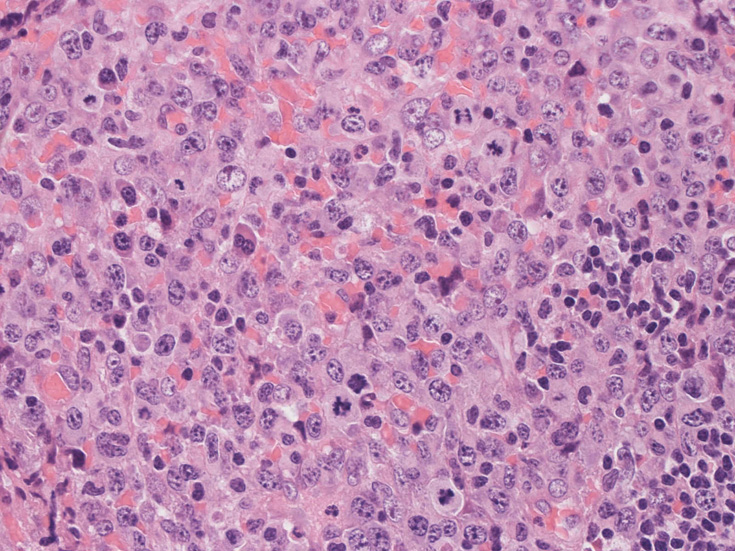

高倍率x400では, 増殖細胞はcentroblastに似て複数の明瞭な核小体をもった淡明な大型類円ないし卵円形核を持っている。核分裂像が多い。この症例では多型はめだたない。典型的な腎臓型のくびれた核を持つ細胞などはない。ALKの形態的variant症例と考えられるが, 化学療法後の再発による影響も否定できない。